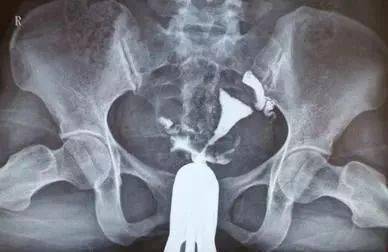

輸卵管造影是輸卵管粘連的一種檢查,做了輸卵管造影之后的女性,一定要遵循醫(yī)囑。

如果不多加注意,會再次使輸卵管發(fā)生堵塞,這時懷孕就比較難了。 1、14天內(nèi)禁止盆浴,性生活。

做完輸卵管造影后,需要禁止盆浴、及性生活兩個星期,適當吃些抗生素,防止感染。 2、造影后少量流血 做完造影檢查之后,7天之內(nèi),女性生殖道會有少許流血現(xiàn)象。

如果流血量很多,超過一個星期,就要提高警惕了,要去醫(yī)院檢查下,看看是否引起感染之類的現(xiàn)象。 3、輸卵管不通假象。

一些女性需要注意,有時候,輸卵管痙攣,會導致輸卵管不通假象,這個不用太過擔心。 4、堅持避孕 做完造影之后,還要注意,要避免3個月,避免引起感染。